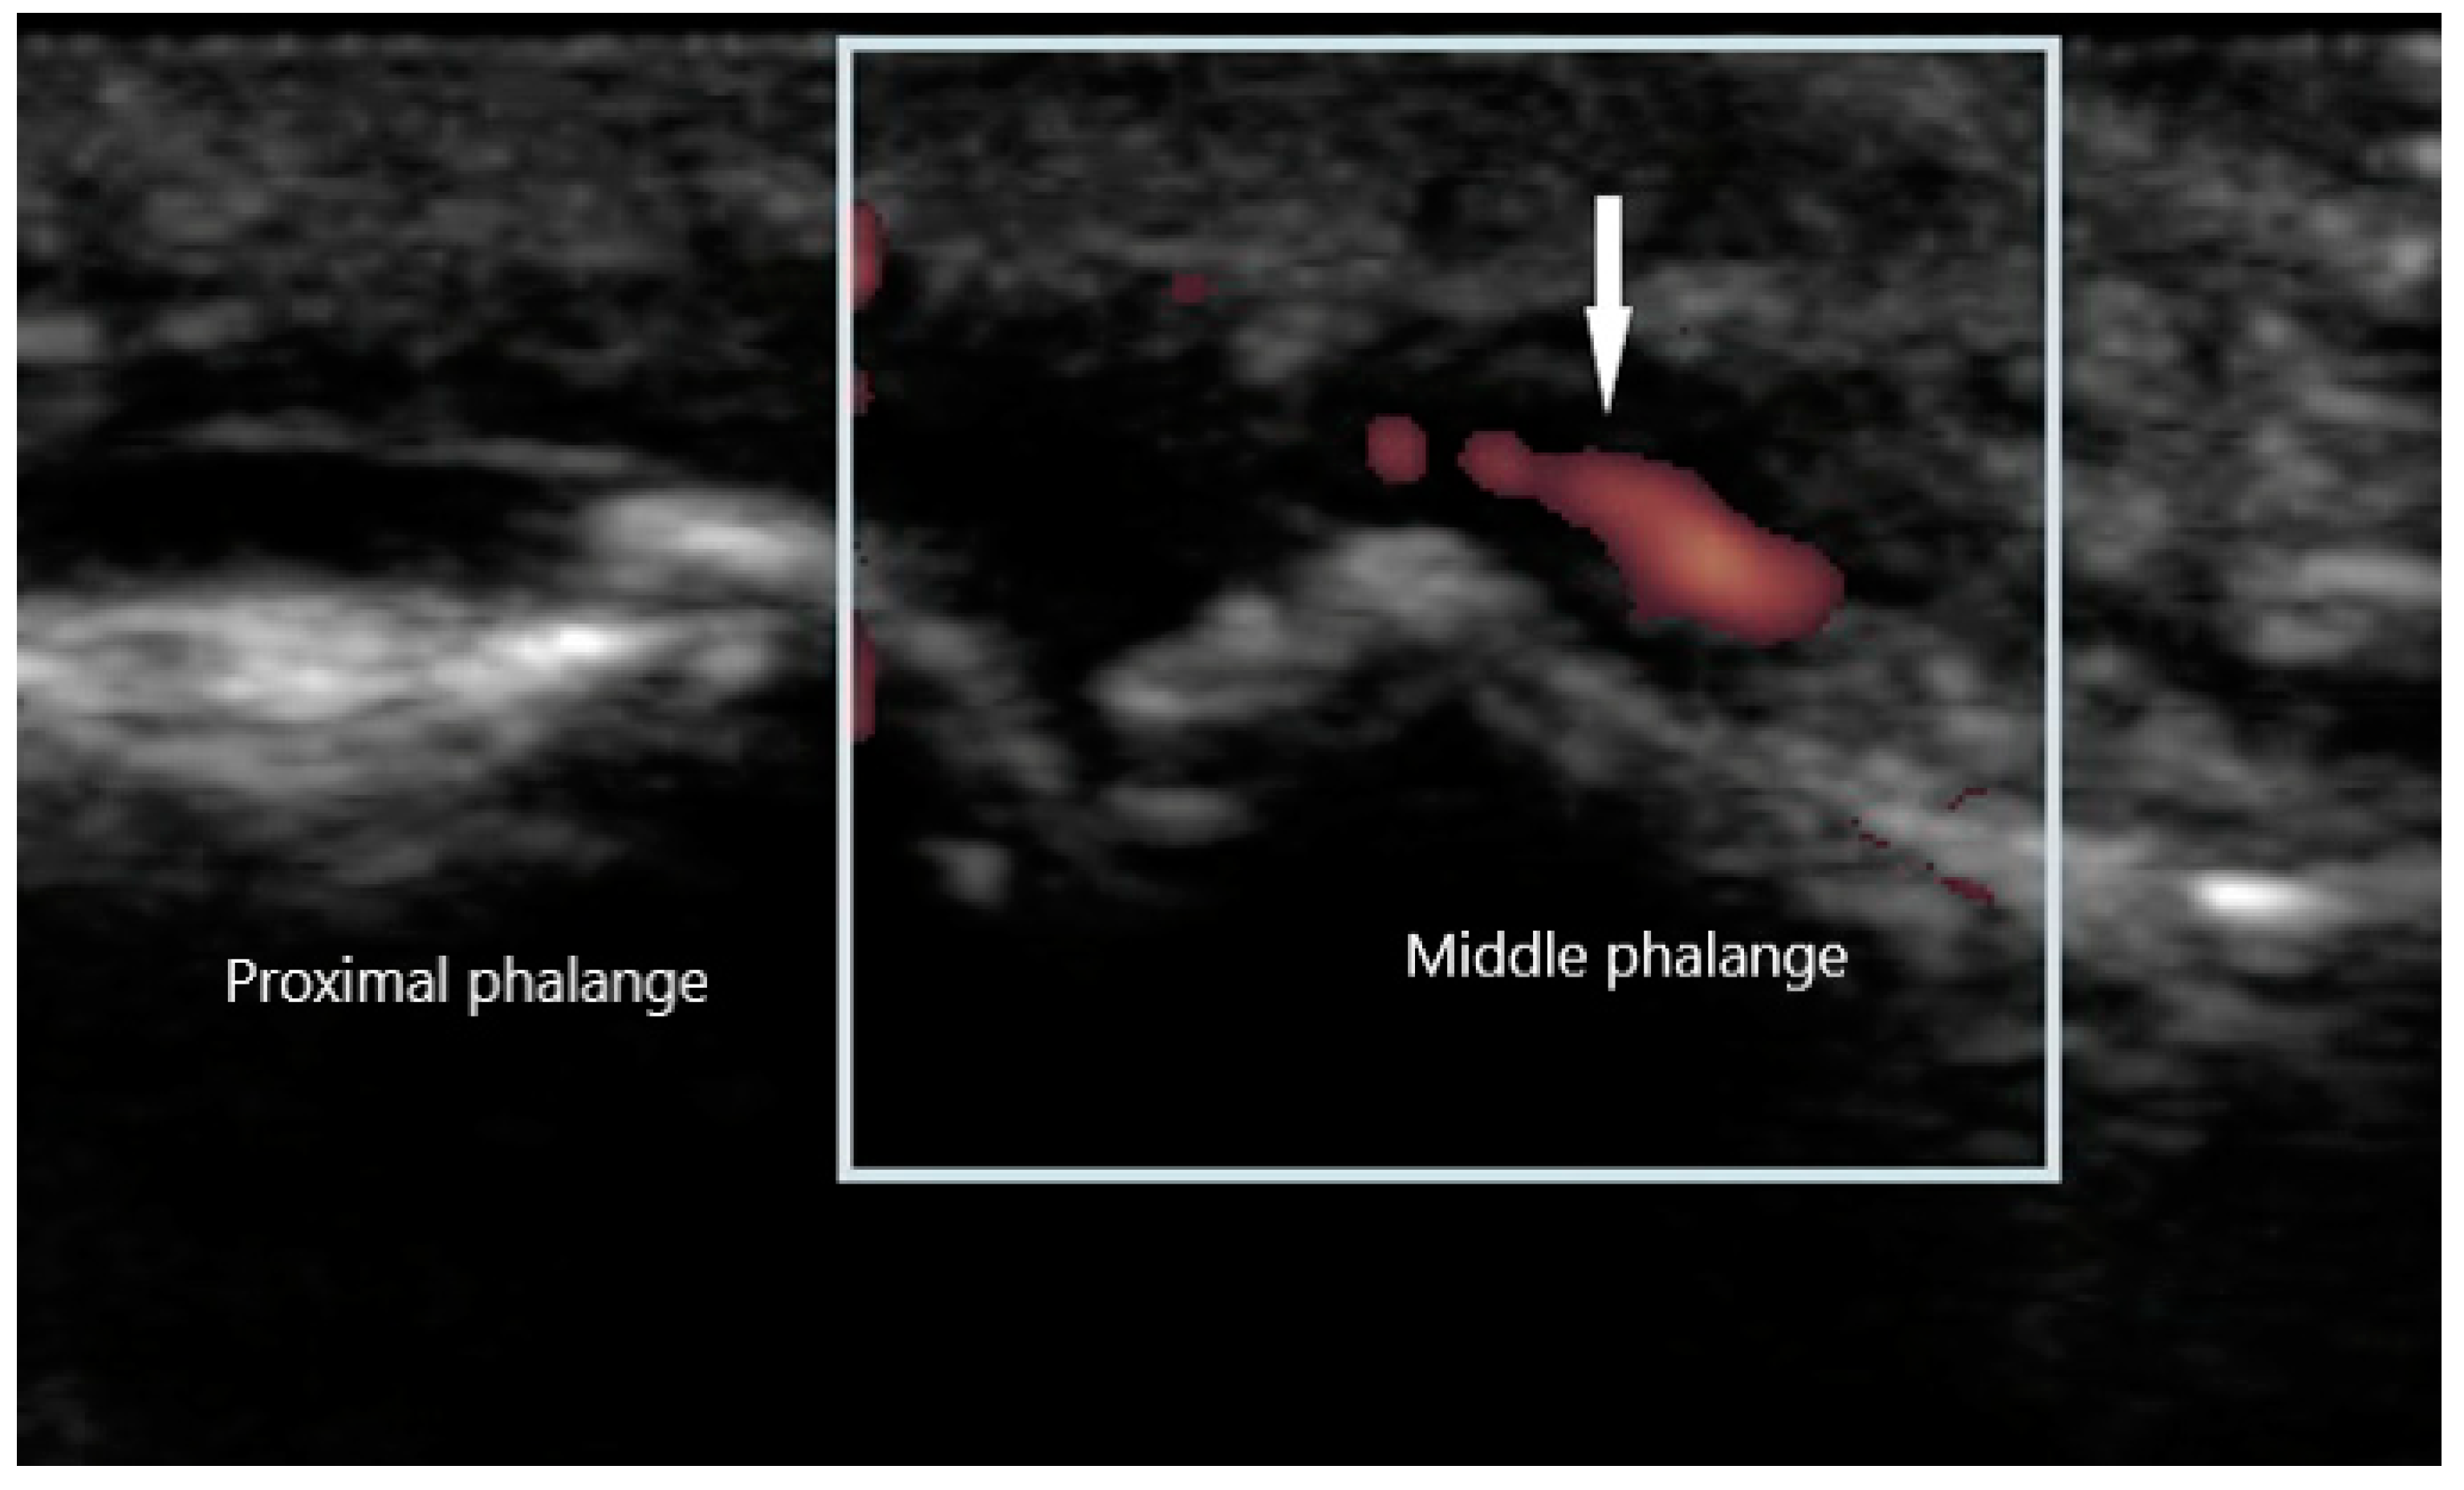

Peripheral joint involvement can be similar between SpA and RA, though the former more commonly presents as asymmetric oligo-arthritis. SpA, especially psoriatic arthritis, may also affect the DIP joints, which is a feature never seen in RA. Furthermore, tendinous and peritendinous structures are more often affected, as is seen in dactylitis and enthesitis. Sonographic characteristics of peripheral joint inflammation in SpA are also similar to that of RA, both in greyscale and power Doppler (Figure 5). Joint effusions are compressible, displaceable, and hypoechoic substances within the joint space, while synovitis is a non-compressible, non-displaceable thickening of the synovium. Hyperemia on power Doppler may also be present. Enthesitis is inflammation of the insertion of ligament, fascia, or tendon into bone. The most commonly affected entheses are the Achilles tendon (Figure 6), plantar fascia, lateral humeral epicondyle, greater trochanter, and pes anserinus [30]. On physical examination, patients may exhibit pain on palpation or swelling of these structures. Sonographic findings reveal hypoechoic or thickened insertion of the tendon 2 mm or less from the bony cortex. Doppler signal, bone spurs at tendinous insertion known as enthesophytes, calcifications, or erosions may be present [31]. Dactylitis, or “sausage” digits (Figure 7), is a well described yet rare finding in SpA, characterized by diffuse tenosynovitis, synovitis, and enthesitis [32].

Figure 5. Synovitis of proximal interphalangeal joint with power Doppler signal (arrow).